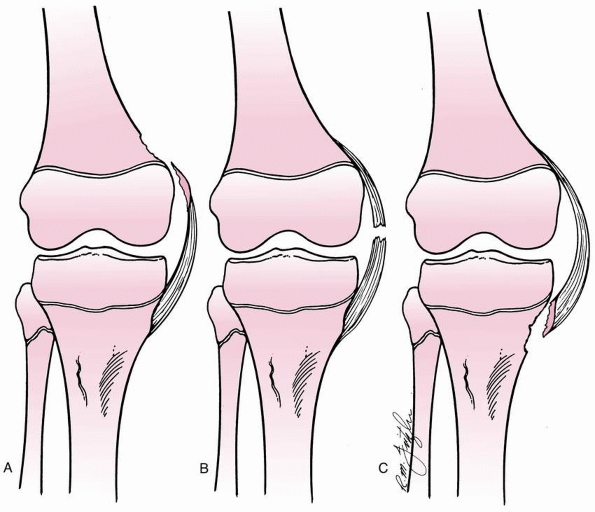

FIGURE 24-2 Classification of tibial spine fractures. A. Type I, minimal displacement. B. Type II, hinged posteriorly. C. Type III, complete separation.

-

Type 1—minimal displacement of the fragment from the rest of the proximal tibial epiphysis

Type 2—displacement of the anterior third

to half of the avulsed fragment, which is lifted upward but remains

hinged on its posterior border in contact with the proximal tibial

epiphysis -

Type 3—complete separation of the avulsed fragment from the proximal tibial epiphysis, with upward displacement and rotation

The interobserver reliability between type 1 and type 2/3 fractures is

good; however, differentiation between type 2 and 3 fractures may be

difficult.175

FIGURE 24-3 Stages of displacement of tibial spine fractures. A. Type I fracture, minimal displacement (open arrow). B. Type II fracture, posterior hinge intact. C. Type III fracture, complete displacement and proximal migration.